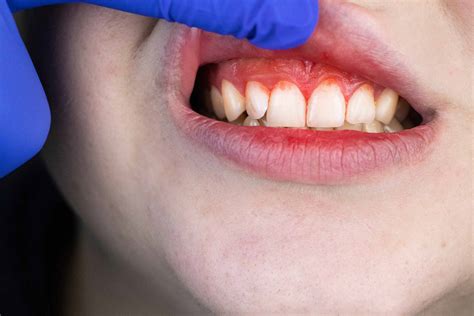

• Gingivitis: The earliest stage where gums are inflamed, sensitive, and prone to bleeding while brushing.

Common Visual Symptoms to Watch For

When you look at resources providing Gum Disease Pictures, you will notice consistent visual markers. Recognizing these early is essential to preventing permanent tooth loss. The following table highlights what you should look for compared to healthy tissue:

Visual Indicator Healthy Gums Signs of Disease

Color Firm, pale pink Deep red, purple, or bright red

Texture Stippled (orange peel texture) Smooth, shiny, or puffy

Margin Snug against the tooth Receding or showing gaps/pockets

Bleeding None Frequent bleeding during brushing